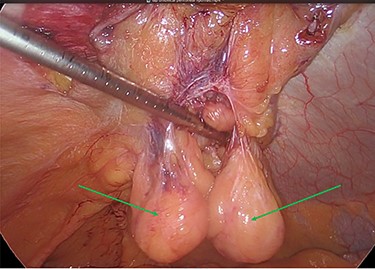

The viable omentum was reduced into the peritoneal cavity. Two lipomas were then observed attached to the parietal peritoneum (Figs 3 and 4). The lipomas were also reduced into the peritoneal cavity from within the hernia sac. Each one was 2 cm in diameter based on laparoscopic visualization using the 1 cm markings on a suction irrigation device.

Reduction of the first peritoneal lipoma (green arrow) into the peritoneal cavity.